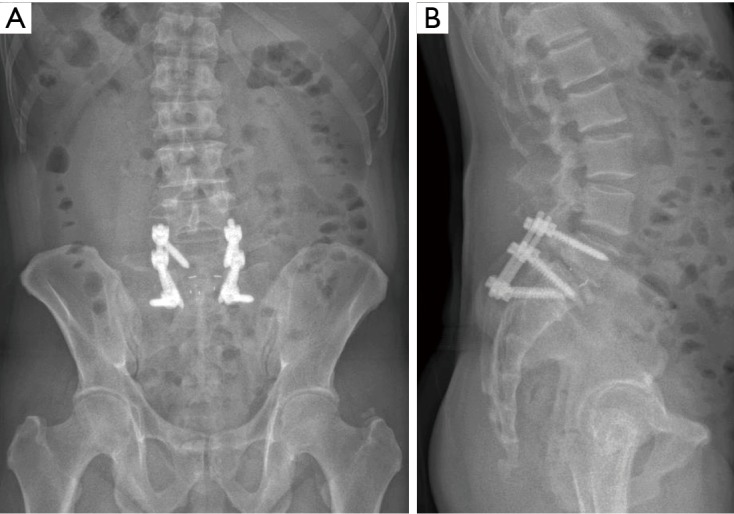

Figure 3.

AP/Lat X-rays of the patient post index surgery.

The patient underwent the index surgery comprising of open bilateral decompression laminectomy, complete bilateral facetectomies, transforaminal lumbar interbody fusion using polyaxial pedicle screw (7.5 mm)-titanium rod (5.5 mm) construct with size 12 mm Polyetheretherketone (PEEK) cage and attempted reduction of the spondylolisthesis at the L5/S1 level. As the deformity remains stiff despite posterior release, decision was made intra-operatively to accept partial reduction of the sagittal deformity. Electromyographic signals were normal throughout the surgery. His immediate post-operative recovery was uneventful and he was discharged on the 4th post-operation day. X-rays taken was shown in Figure 3.